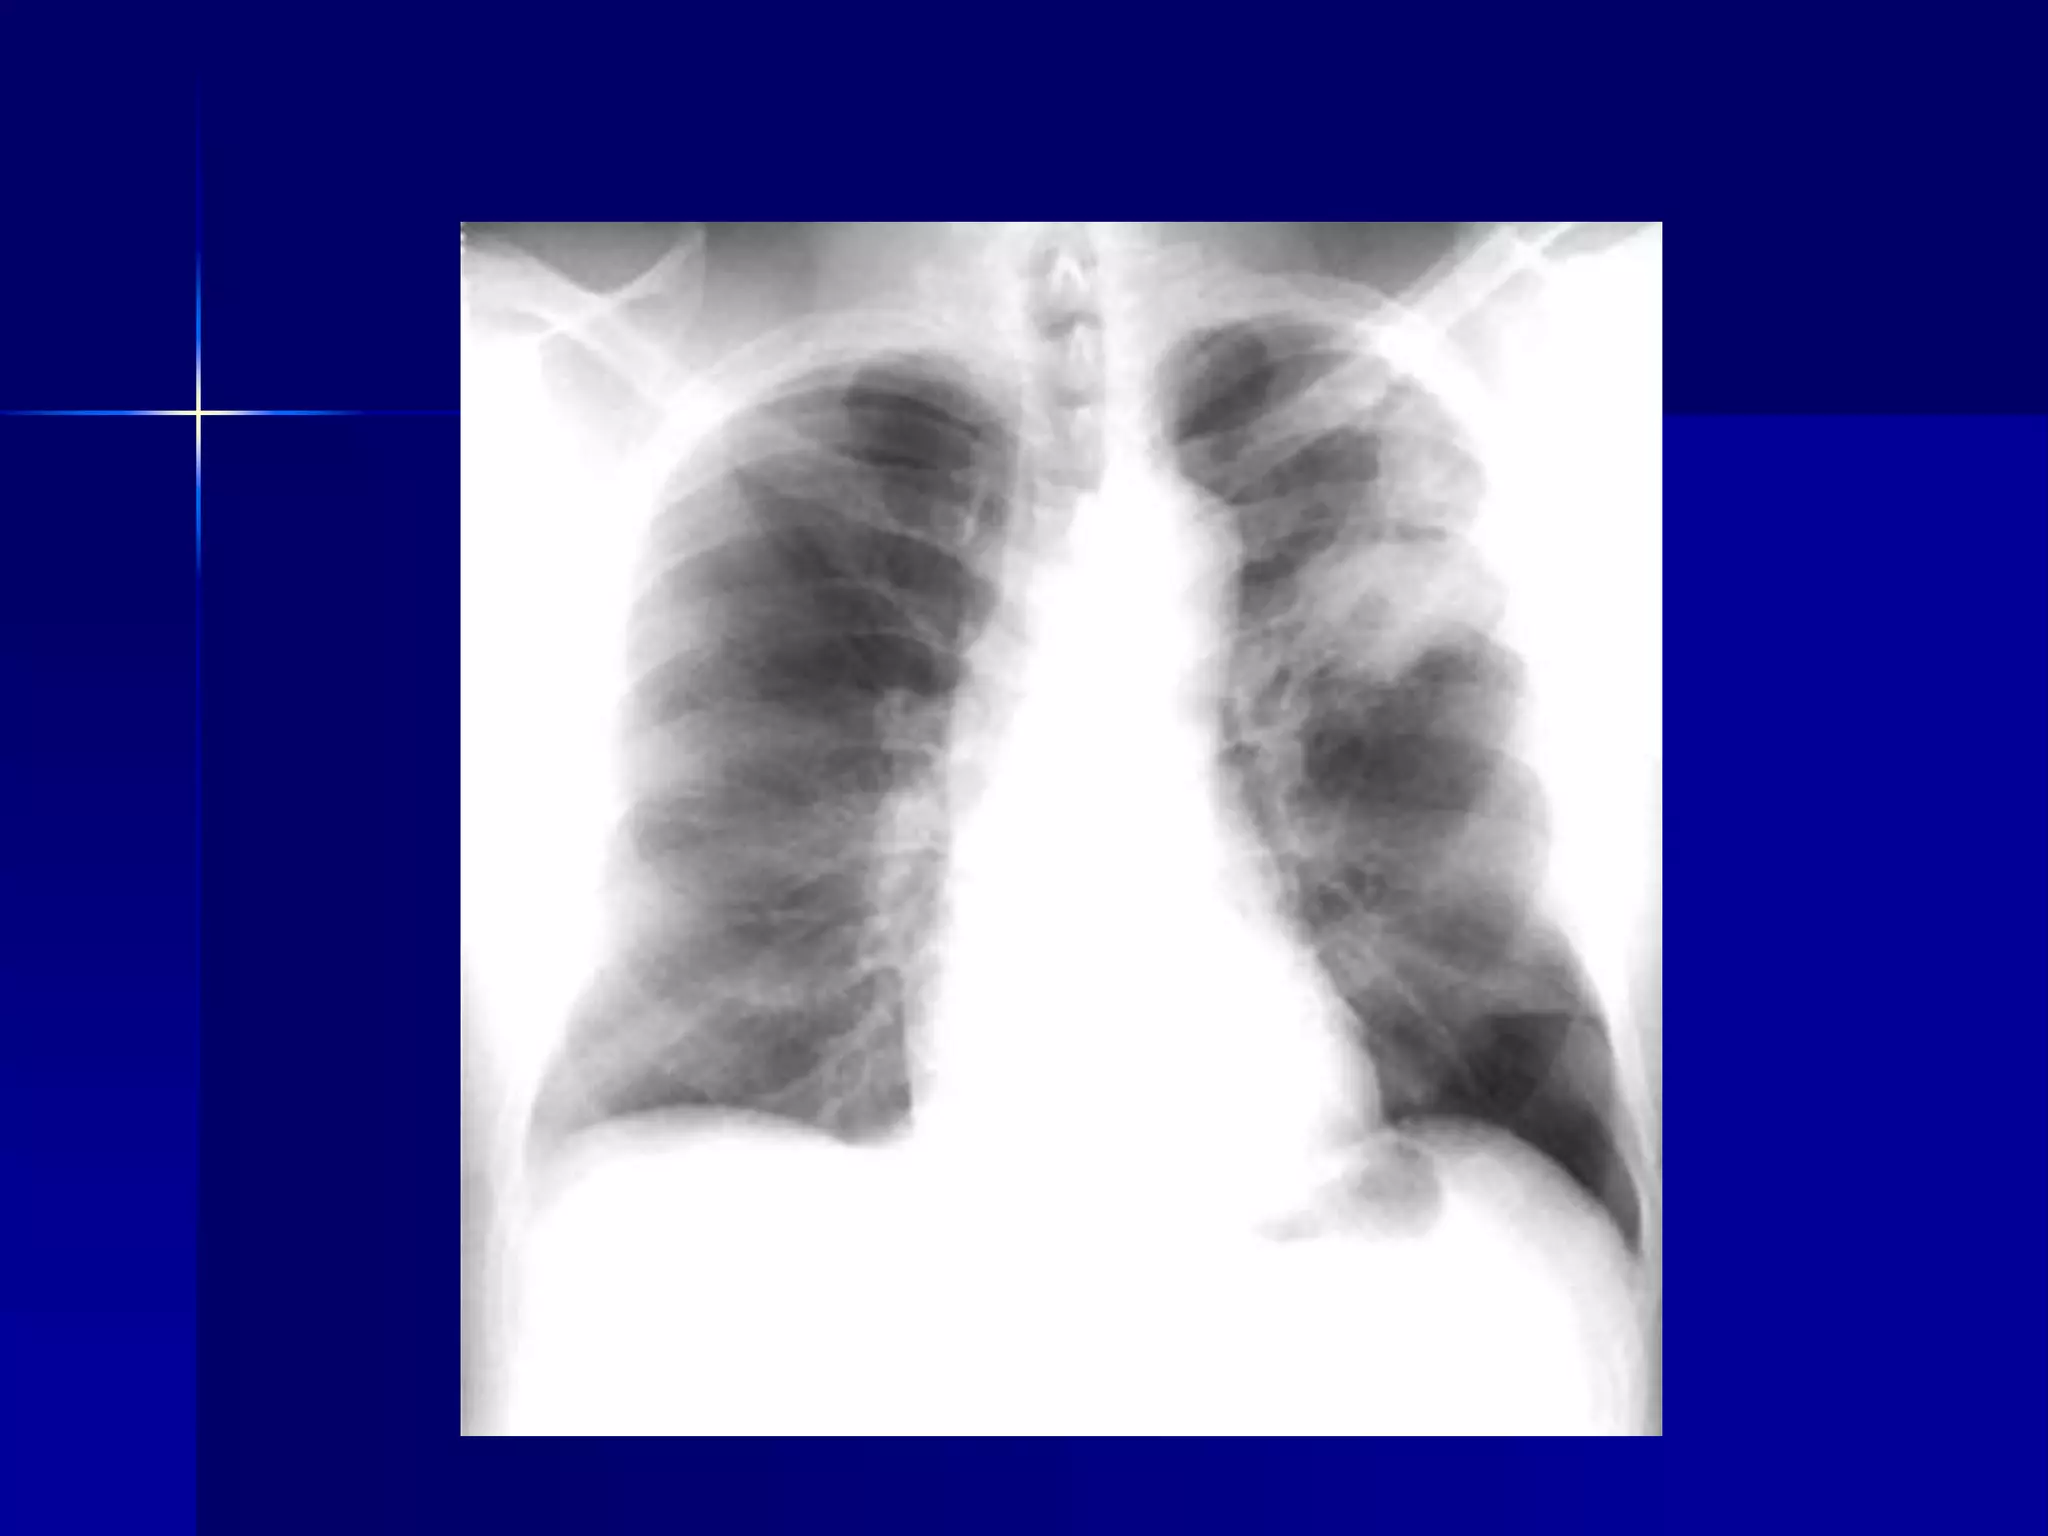

Cystic Fibrosis - Bronchiectasis

 Bilateral diffuse

 Multiple cavities / Bronchiectasis

 Peribronchial fibrosis

 Prominent hilum

 Hyperinflated